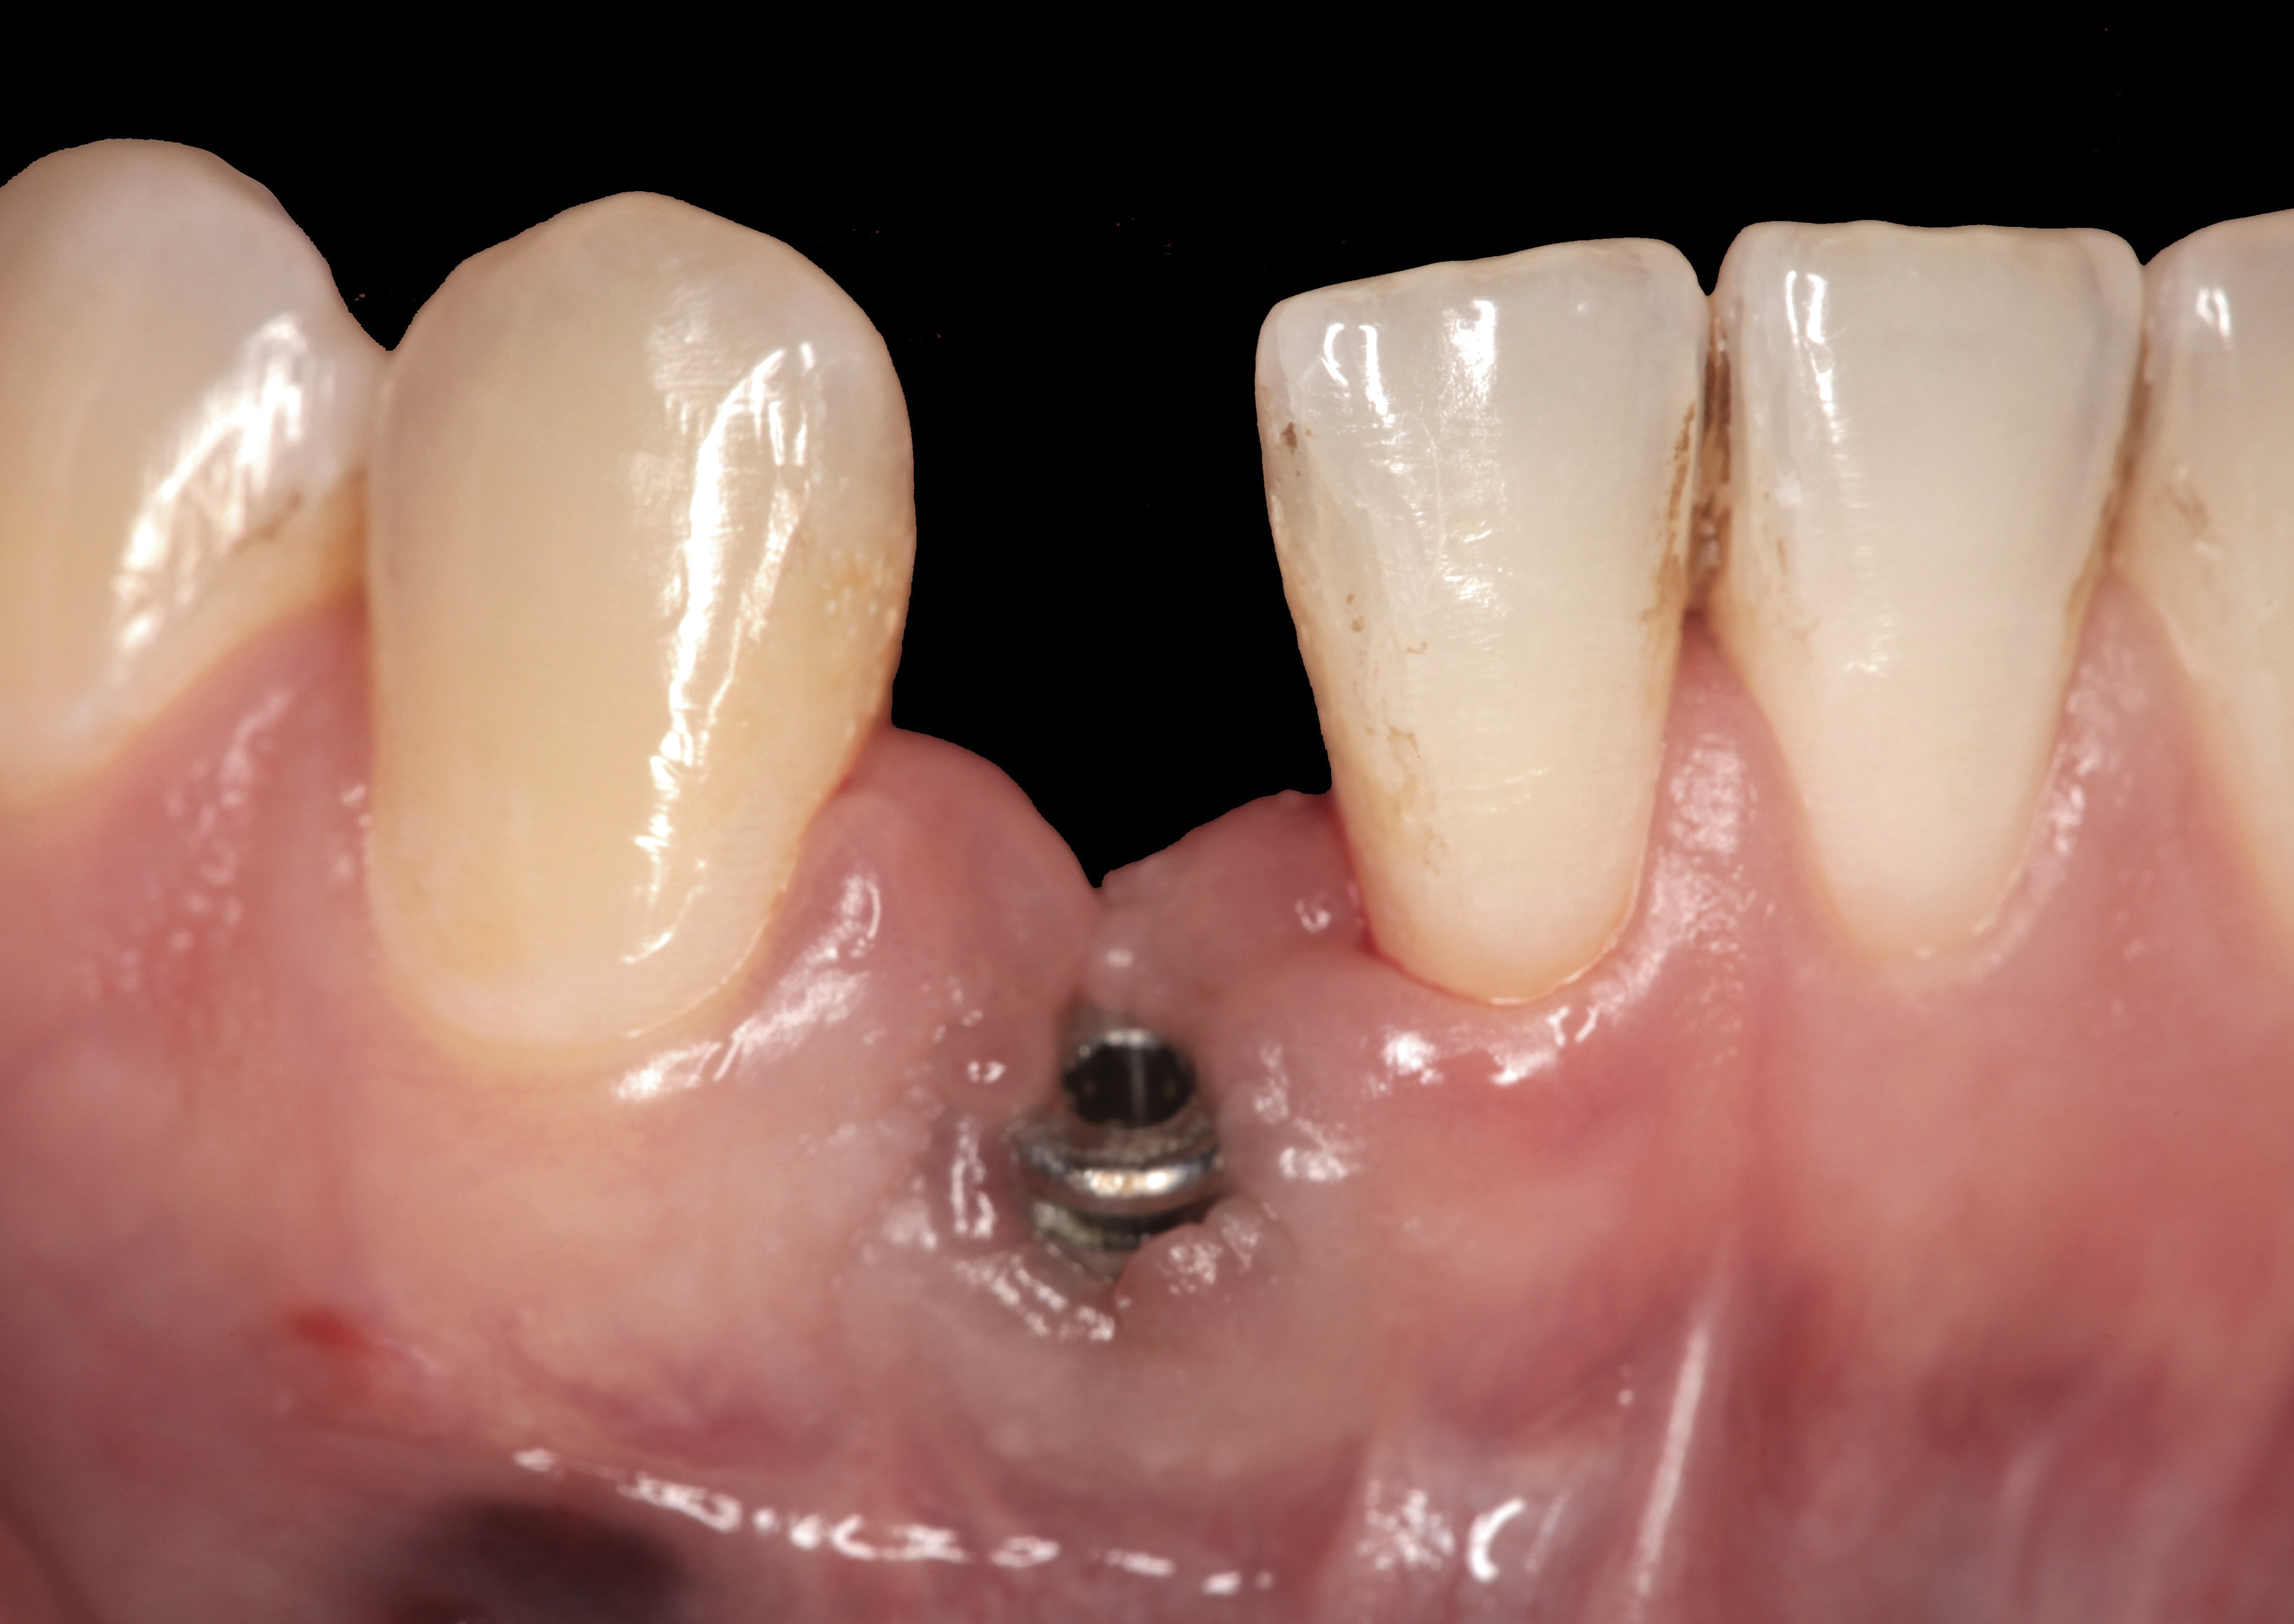

Fig 32. A dissatisfied patient presented with significant midfacial recession of implant restoration of tooth No. 26. Pink ceramic material was used unsuccessfully to prosthodontically compensate for the lost midfacial tissue.

Figure 32

Fig 33. Excessive facial angulation of the implant placement shown with an abutment driver in the access screw hole.

Figure 33

Fig 34. A surgical cover screw was placed in an attempt to decoronate the implant and gain soft-tissue coverage in situ.

Figure 34

Fig 36. Two weeks after RBR placement, the soft tissue did not adequately cover the implant. The problem was in poor implant angulation and proper depth to allow the soft tissues to cover over.

Figure 36